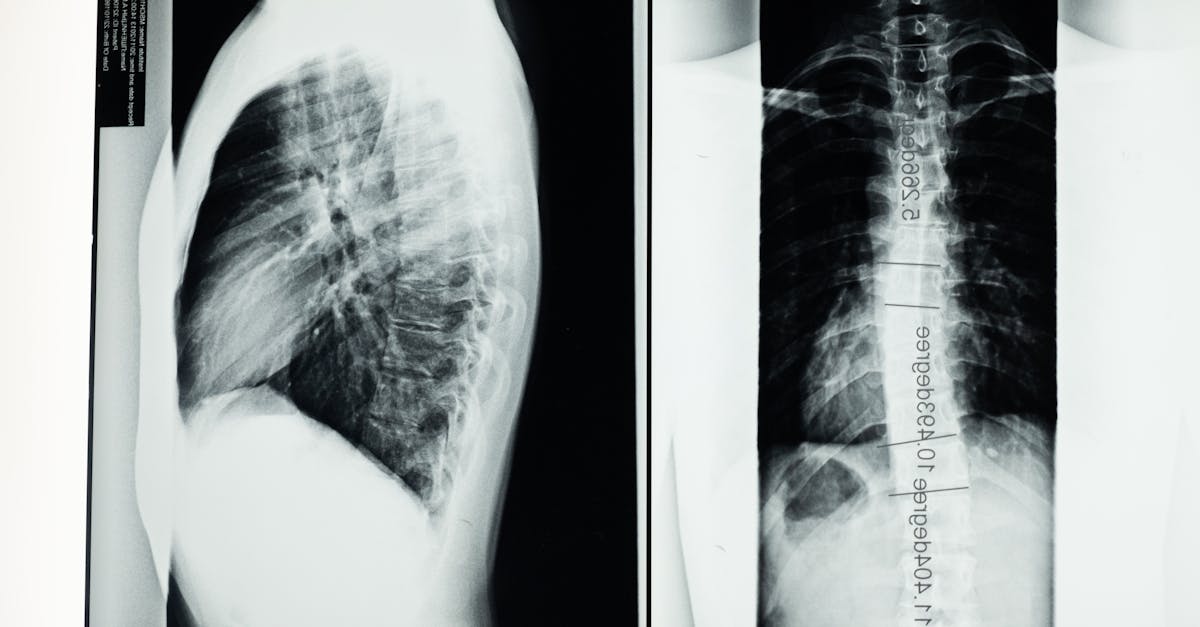

La décompression neurovertébrale est une technique innovante qui joue un rôle clé dans l’amélioration de la flexibilité de la colonne vertébrale à long terme. En appliquant une traction contrôlée sur les vertèbres, cette méthode crée des espaces entre celles-ci, réduisant ainsi la pression sur les disques intervertébraux et les nerfs environnants. Cette séparation favorise une meilleure circulation sanguine, essentielle pour nourrir les tissus vertébraux et contribuer à leur régénération. En améliorant l’élasticité des disques, la décompression aide à maintenir une colonne vertébrale souple et fonctionnelle, permettant ainsi des mouvements plus fluides et réduisant les risques de blessures. De plus, une colonne vertébrale mieux alignée et moins comprimée soutient une meilleure posture, ce qui contribue également à une flexibilité accrue sur le long terme.

La décompression neurovertébrale repose sur un principe fondamental : réduire la pression intra-disque et améliorer l’alignement des vertèbres. En exerçant une traction ciblée, cette méthode permet de créer des espaces entre les vertèbres. Ce processus diminue la compression sur les nerfs et favorise la circulation sanguine vers les tissus vertébraux. L’augmentation du flux sanguin contribue à optimiser l’apport en O2 et en nutriments, essentiels pour le maintien d’une colonne vertébrale souple et dynamique.

Un aspect fondamental de la décompression neurovertébrale est qu’elle facilite la régénération et l’hydratation des disques intervertébraux. En permettant aux disques de retrouver leur volume et leur élasticité, les vertèbres bénéficient d’un meilleur amortissement contre les impacts. Des disques bien hydratés préservent également la mobilité vertébrale, contribuant ainsi à une flexibilité accrue. Les disques intervertébraux fonctionnent comme des amortisseurs, ce qui réduit l’impact des mouvements quotidiens et des activités physiques.